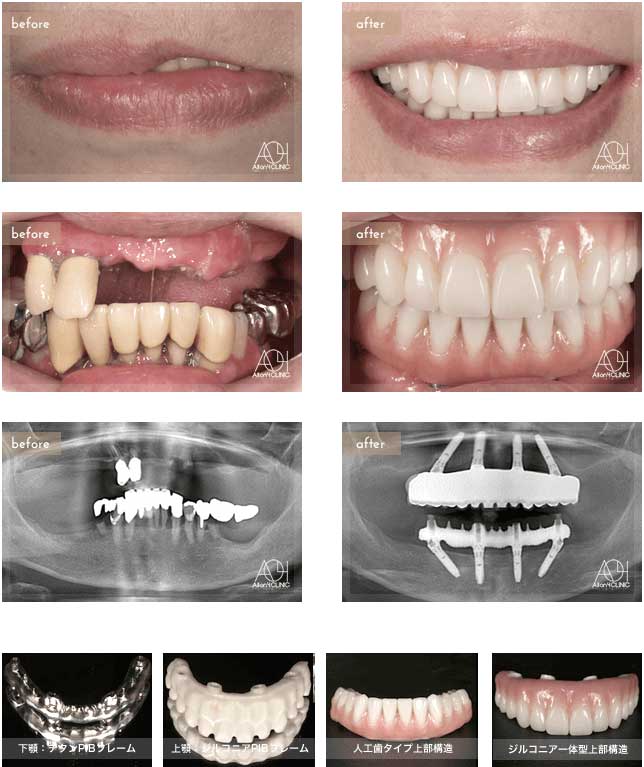

Treatment : All-on-4

- Upper All-on-4

- Lower All-on-4

Age : 62 Sex : 女 Y.M

| 主訴 | 入れ歯が合わなく痛いし、入れ歯を入れている事が嫌になってしまった。 |

| 治療内容 | X-guide(エックスガイドナビゲーションシステム)を用いてインプラントを正確に埋入。 上下オールオン4。 |

| 治療費(総額) | ¥7,200,000(税抜)『モニター割引適用』 |

| リスク | 治療後の口腔管理が不適切な場合、埋入したインプラント周囲に感染・炎症を起こし、脱落する可能性がございます。 |